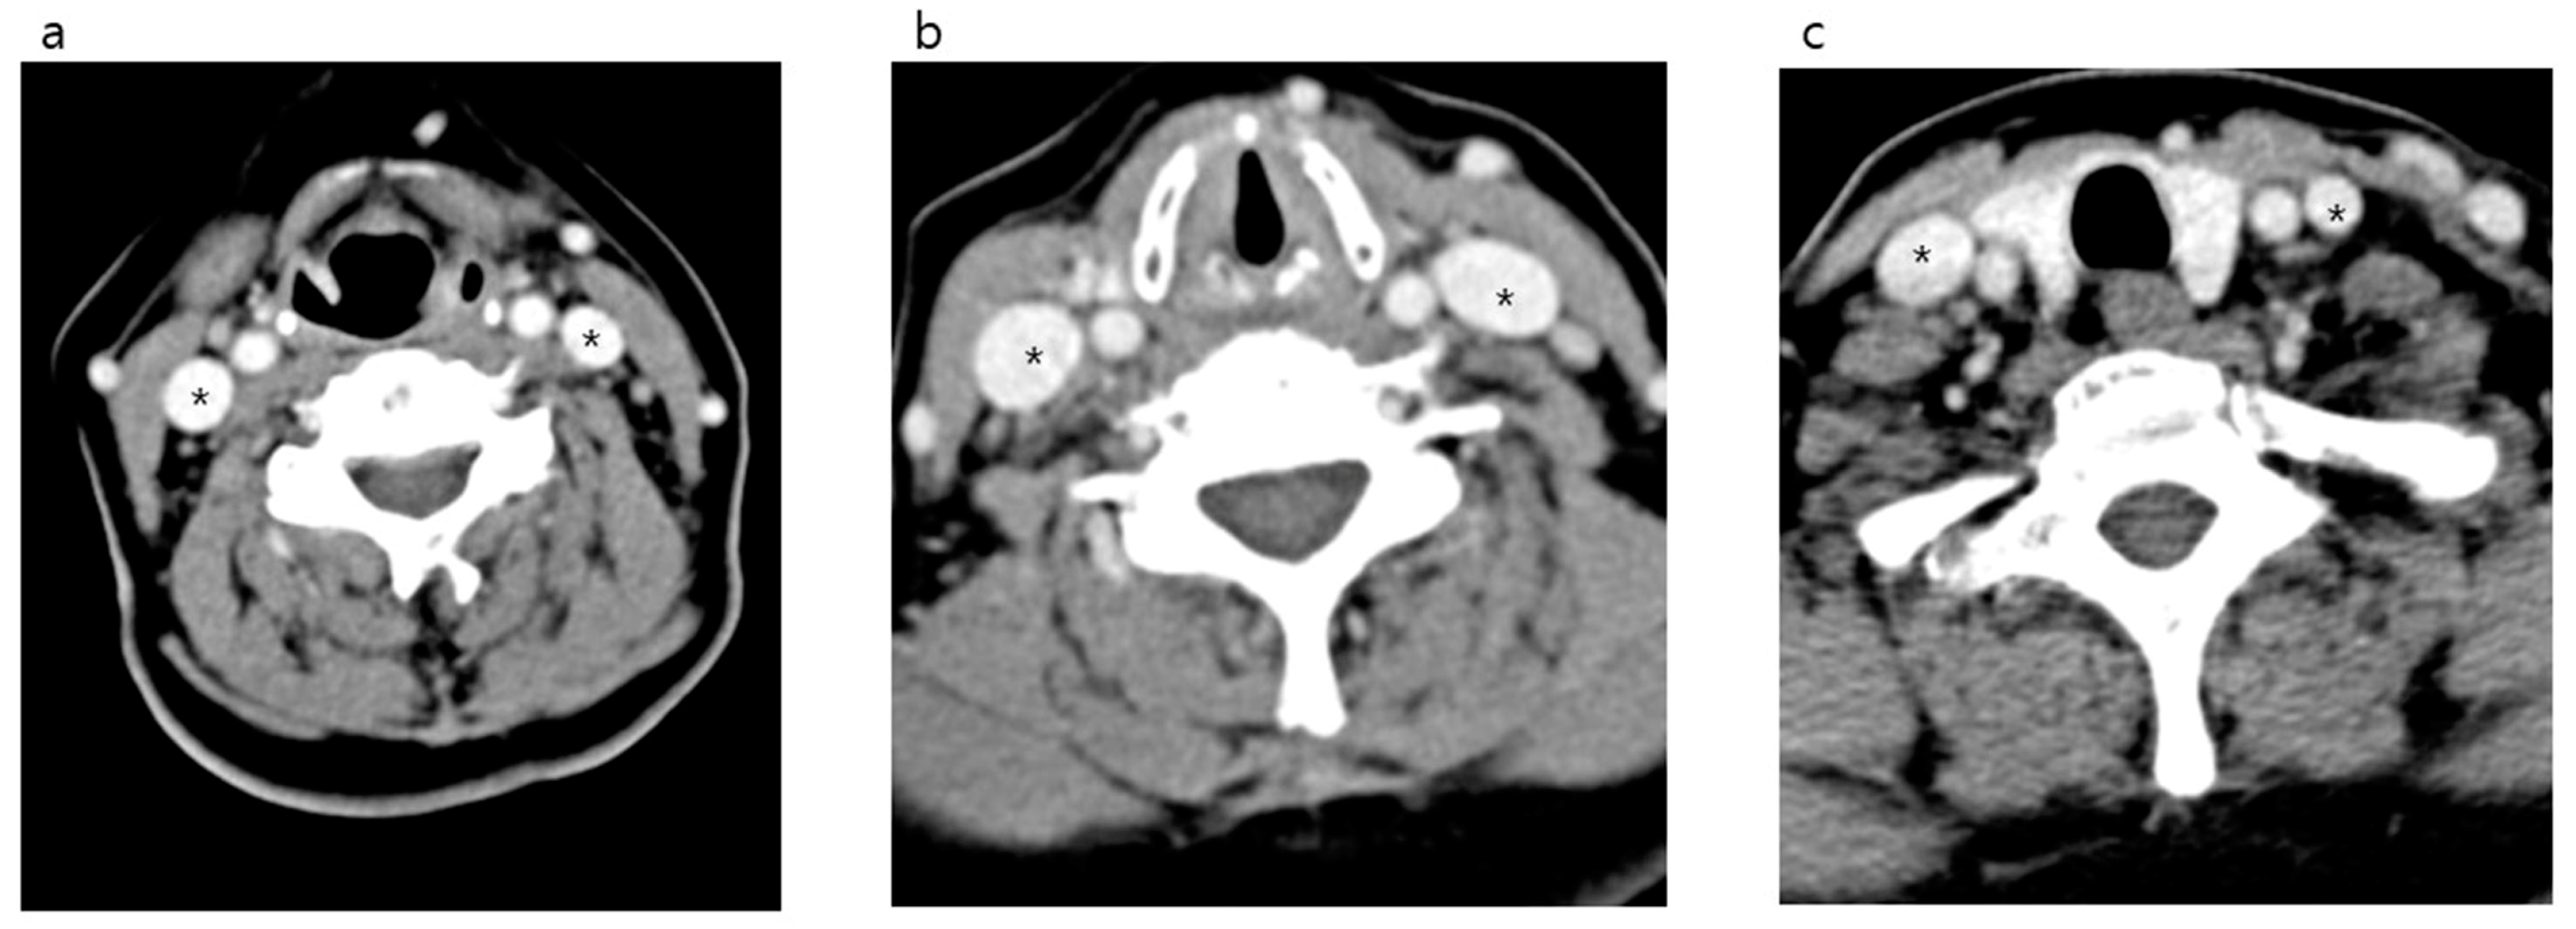

| Middle | Diameter (mm) | 16.0 (13.0–19.9) | 17.6 (14.8–20.9) | 14.4 (11.8–17.5) | <0.001 | 0.73 |

| Area (mm2) | 158.5 (105.8–226.7) | 190.8 (137.2–258.0) | 127.0 (88.0–180.2) | <0.001 | 0.73 | |

| Lower | Diameter (mm) | 13.9 (11.4–17.3) | 16.5 (14.2–19.1) | 11.8 (10.2–13.8) | <0.001 | 0.77 |

| Area (mm2) | 127.4 (89.0–196.3) | 183.1 (127.6–241.6) | 94.5 (68.7–126.7) | <0.001 | 0.19 |

| Right | Diameter (mm) | 14.3 (12.3–16.8) | 17.6 (14.8–20.9) | 16.5 (14.2–19.1) | <0.001 |

| Area (mm2) | 124.3 (98.7–176.2) | 190.8 (137.2–258.0) | 183.1 (127.6–241.6) | <0.001 | |

| Left | Diameter (mm) | 12.0 (10.2–14.6) | 14.4 (11.8–17.5) | 11.8 (10.2–13.8) | <0.001 |

| Area (mm2) | 89.1 (65.1–124.9) | 127.0 (88.0–180.2) | 94.5 (68.7–126.7) | <0.001 |